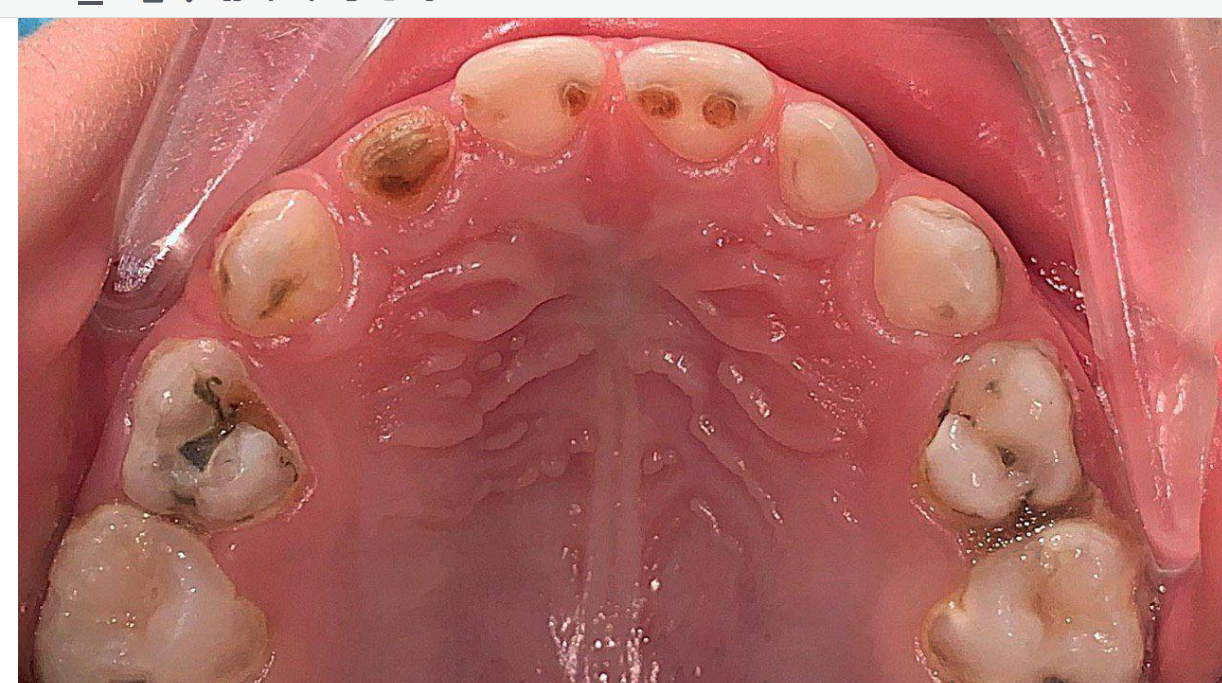

Пульпит — воспаление нервной ткани зуба — у детей встречается не реже, чем у взрослых. Однако лечение молочных зубов имеет свои особенности: зубы малышей не только меньше и мягче, но и играют важную роль в формировании правильного прикуса и сохранении пространства для постоянных зубов.

Молочные зубы отличаются от постоянных:

- дентин тоньше и мягче;

- корни рассасываются естественным образом перед сменой зуба;

- инфекция может быстро распространяться в костную ткань;

- боль ощущается острее из-за чувствительной пульпы.

Поэтому лечение пульпита у детей должно быть минимально инвазивным, чтобы сохранить зуб до естественной смены, предотвратить осложнения и снизить стресс.